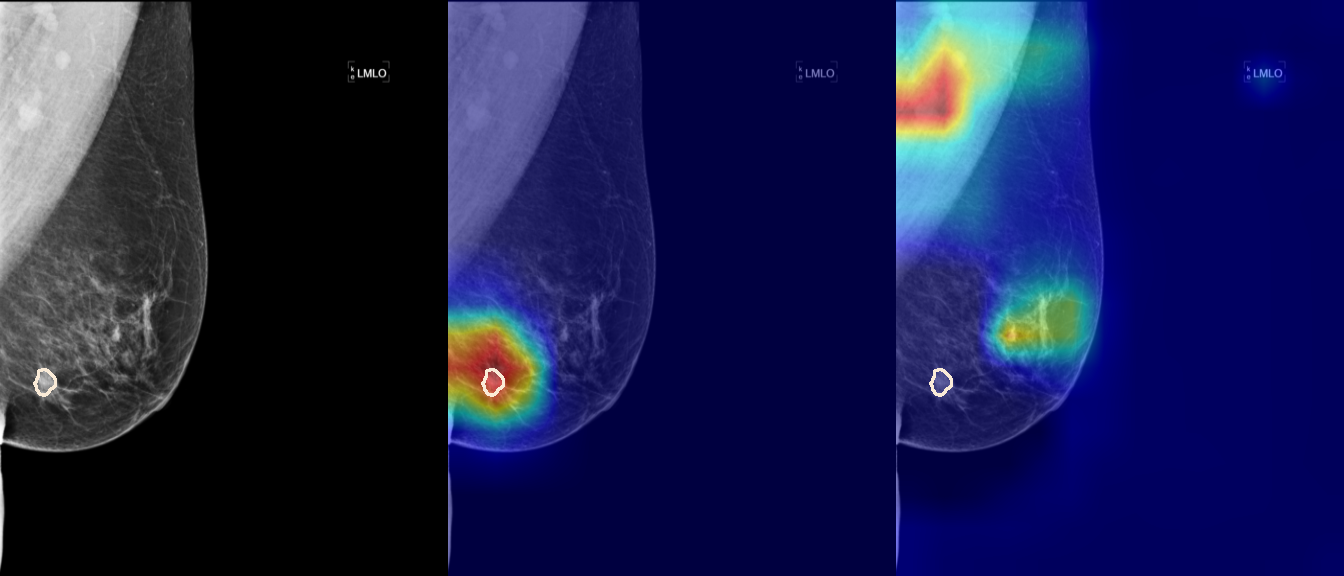

To interpret the decision-making process behind the quantitative results, we visualized Class Activation Maps (CAM) for the top-performing methods, ERM and VREx. Figures 1 through 2 illustrate discriminative regions identified by the models within the full mammograms.

Localization of Clinical Features: A key concern in medical AI is whether high performance stems from genuine pathology detection or spurious background correlations. Our visualizations suggest that Standard ERM achieves its superior quantitative performance by predominantly prioritizing clinical cues. As shown in the top rows of the Figure 1 and Figure 2, the ERM-trained models consistently focus attention on the specific lesion regions within the breast tissue. This demonstrates that despite lacking explicit invariance constraints, ERM is capable of learning robust, medically relevant features when trained on diverse multi-source data.

Attention Drift in Both Methods: While both ERM and VREx generally identify the correct region of interest in successful cases, neither method is immune to attention drift. We observe instances in both training paradigms where the model focuses on irrelevant areas, such as healthy fibroglandular tissue or background artifacts (e.g., rows 5 and 6 in Figure 1). This indicates that while VREx is designed to penalize instability, it does not guarantee perfect anatomical focus compared to the unconstrained ERM baseline.